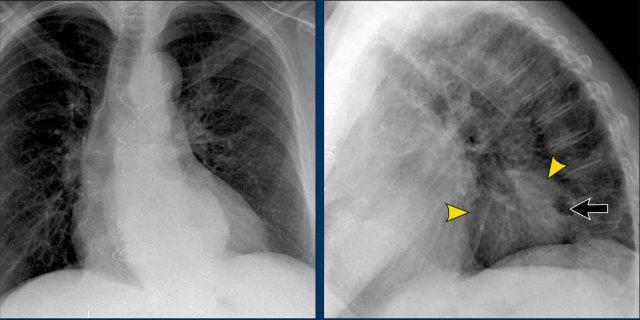

Dấu hiệu Silhouette – Phân tích Phim Nghiêng

Ca lâm sàng 3: Tư thế Nghiêng

- Có tăng độ mờ trên vùng cột sống ngực dưới.

- Phân tích kỹ đường bờ cơ hoành trên phim nghiêng giúp định khu tổn thương:

- Đường bờ vòm hoành phải không quan sát được ở phía sau, gợi ý sự hiện diện của tổn thương có tỷ trọng nước ở thùy dưới phải.

- Tiếp tục xem phim tư thế PA…

Phim PA của Cùng Bệnh nhân

- Bờ tim phải còn nguyên vẹn, xác nhận tổn thương không nằm ở phía trước—phù hợp với phim nghiêng.

- Câu hỏi: Tại sao bóng silhouette của vòm hoành phải vẫn còn nhìn thấy trên phim PA?

- Trả lời: Phần cơ hoành nhìn thấy được trên phim PA đại diện cho điểm cao nhất ở phía trước, vùng này không tiếp xúc với đám viêm phổi ở phía sau thùy dưới phải. Do đó, bóng silhouette bình thường và dấu hiệu silhouette vắng mặt.